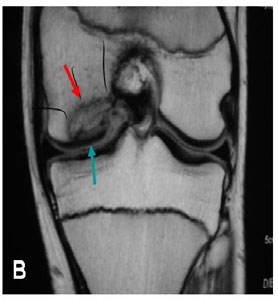

Cartilage lesion of the knee are classified from I (one) to IV (four) depending upon the depth of the cartilage involved and the severity of the lesion. In grade I lesions, the cartilage has a soft spot. Grade II lesions show minor tears in the surface of the cartilage. Grade III lesions have deep crevices. In grade IV lesions, the tear goes all the way up to the underlying bone.

The following images show each type of defect:

The grade IV lesion goes completely through all layers of the cartilage. It is diagnosed as a full-thickness lesion. Sometimes part of the torn cartilage breaks off inside the joint and begins to move around within the joint, causing even more damage to the surface of the cartilage.